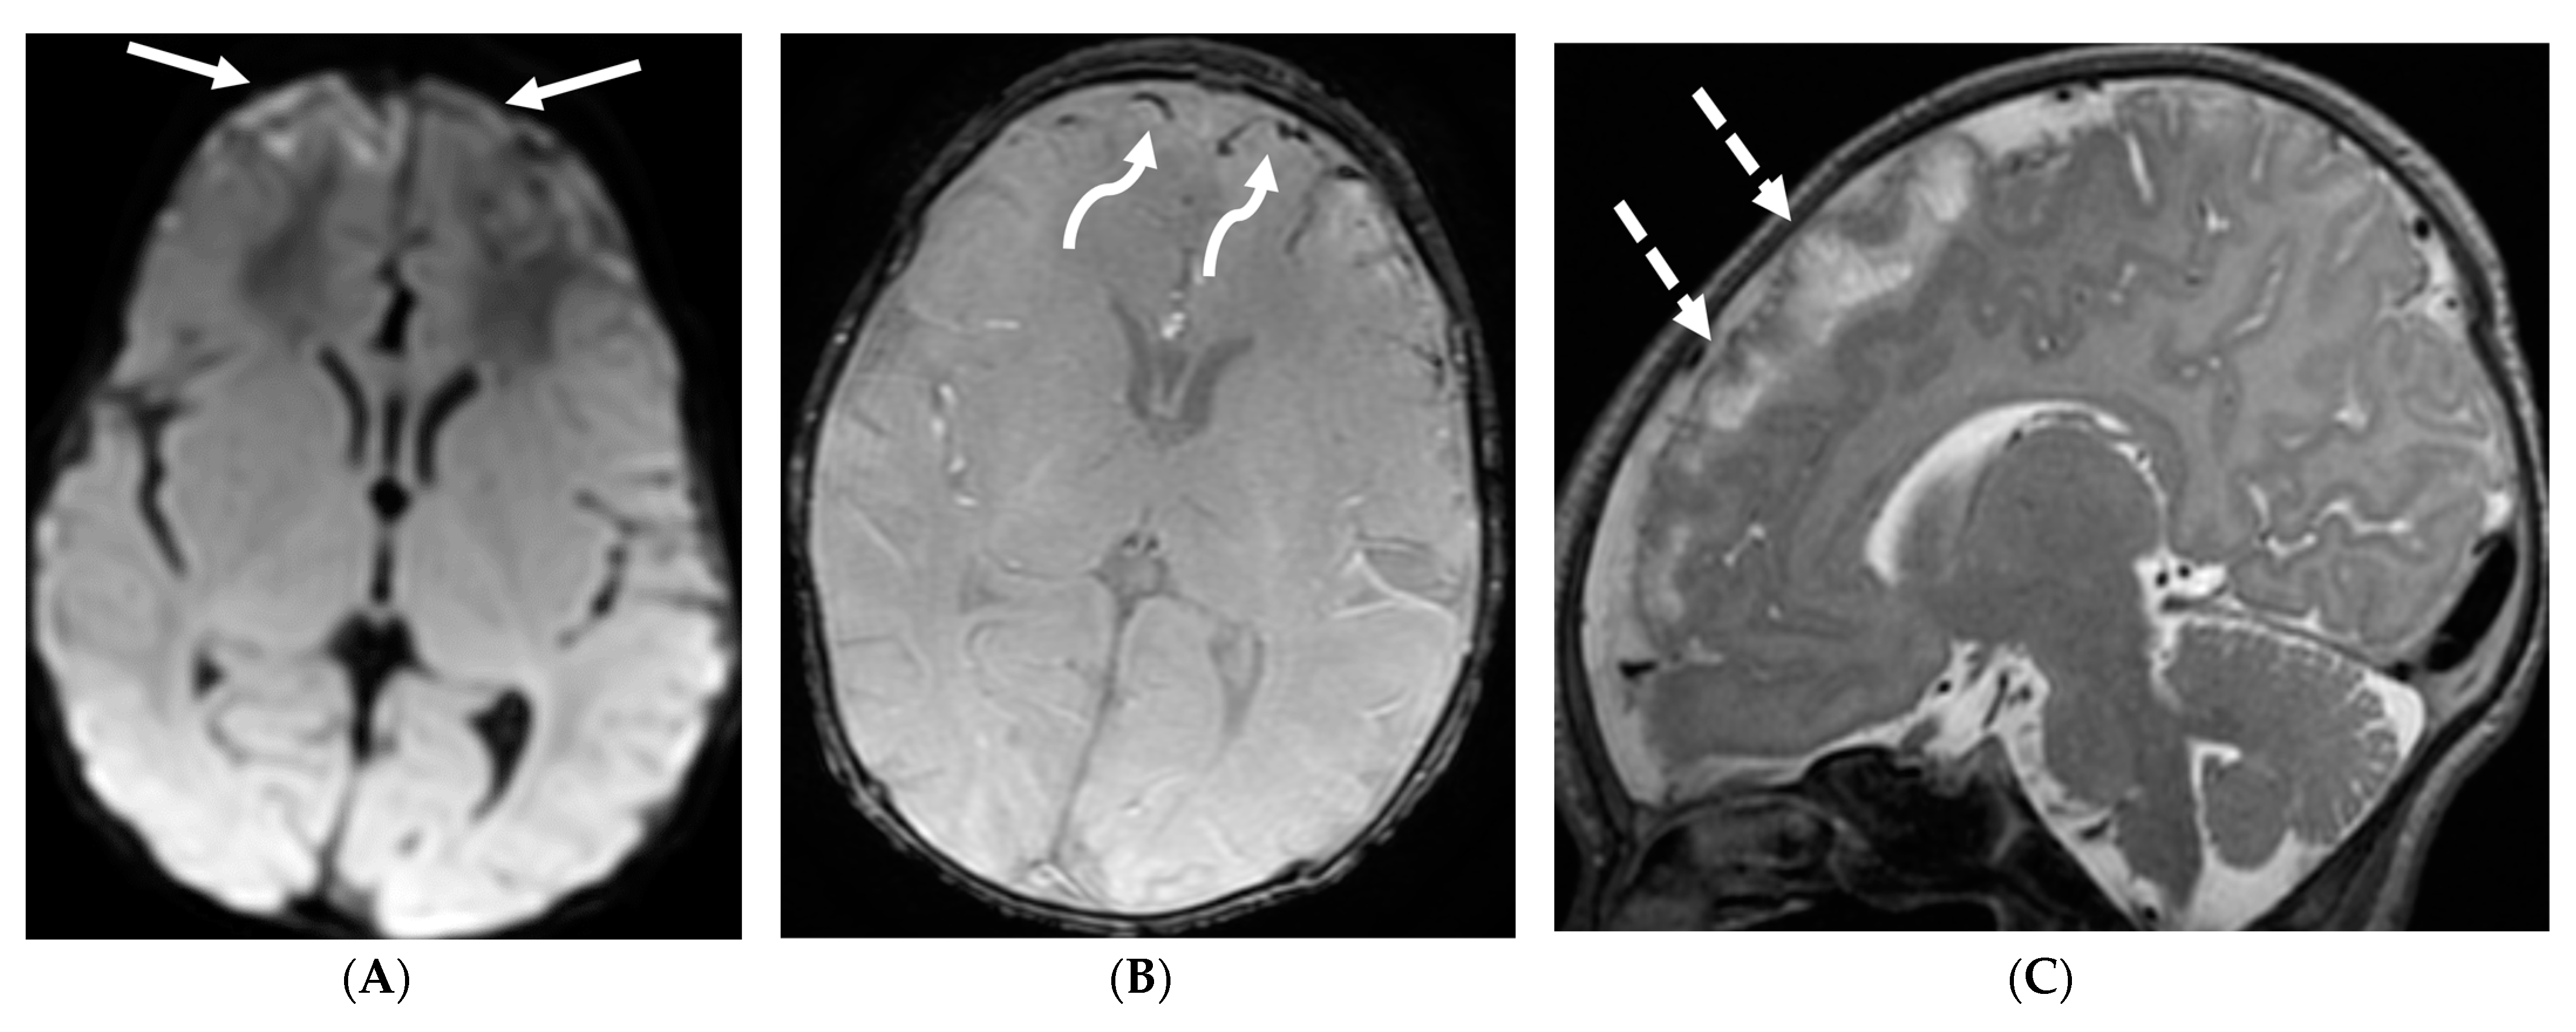

Figure 12.

Axial DWI (A), axial SWI (B), sagittal T2 (C), axial ASL (D) and coronal T1 post contrast (E): 11-day-old female presented with seizures and lethargic. Restricted diffusion is noted in the sulci along the bilateral frontal convexities, concerning for meningitis (arrows). Curvilinear susceptibility in the extra-axial spaces of bilateral frontal convexities, consistent with thrombosed cortical veins (curved arrows). Cortical T2 hyperintensity is seen in the bilateral frontal and parietal lobes with corresponding hyperperfusion in keeping with extensive cerebritis (dashed arrows). Diffuse leptomeningeal and pachymeningeal enhancement is seen (open arrows). Overall features represent meningitis and cerebritis. Cerebrospinal fluid analysis: Group B streptococcus.